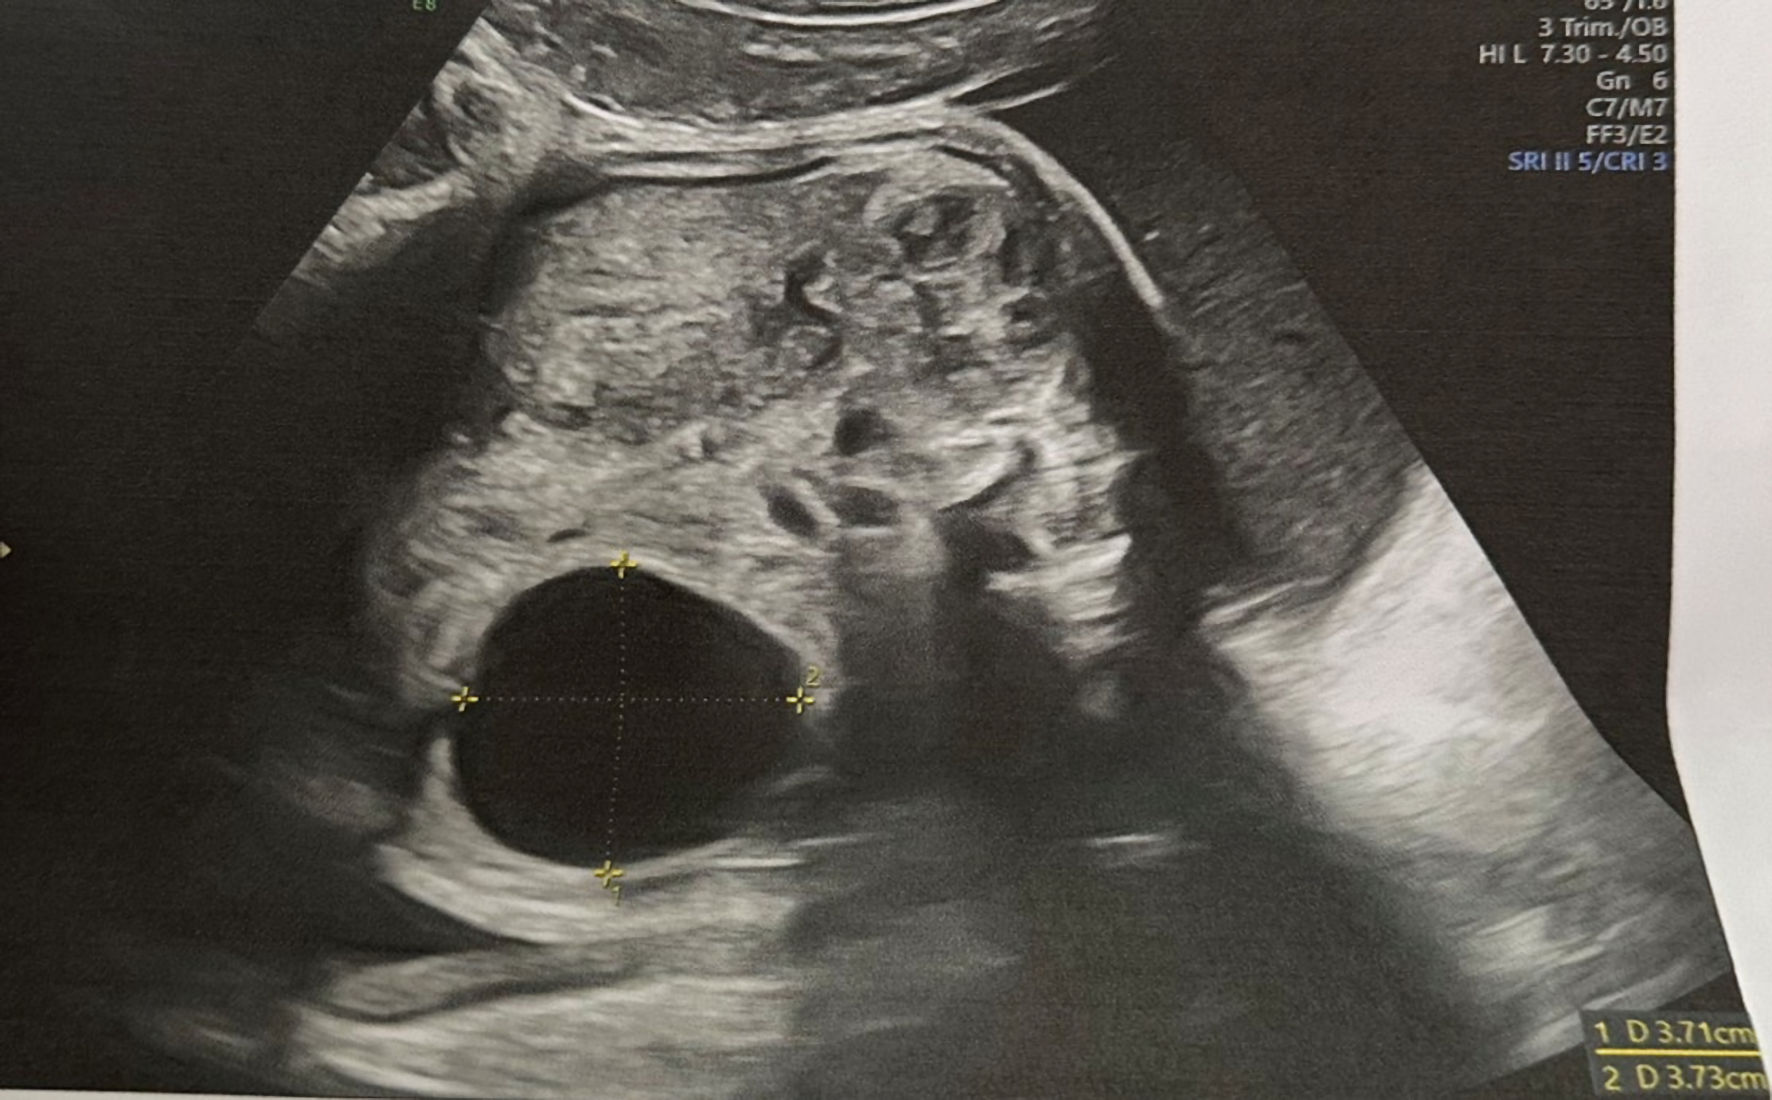

A repeat sonography at 27 weeks noted a fetal abdominal cyst. The patient was referred for comprehensive evaluation and management. A specialist of fetal medicine confirmed the presence of fetal cystic formation in the lower abdomen. The examination revealed female gender with normal biometry, normal appearance of kidneys, urinary bladder and gastrointestinal tract. A left-sided unilocular thin-walled cyst was identified separate from stomach and kidneys. The measurements of the cyst were 37 × 37 mm (Fig. 1). The volume of amniotic fluid was within the normal range, and no hydropic changes were observed in the fetus.

Click for large image

Figure 1. Simple thin-walled cystic formation localized separately from kidney seen in 27th week of gestation.

Due to the specific ultrasound image and localization of the formation, normal appearance of gastrointestinal and urinary tracts, and the female gender of the fetus, a diagnosis of simple ovarian cyst was made.